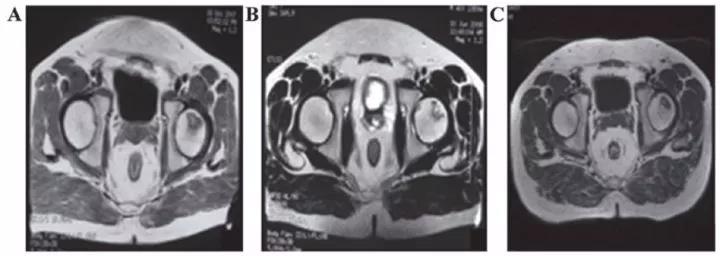

8、泌尿生殖系統(tǒng)疾病

? 勃起功能障礙

運(yùn)用干細(xì)胞治療勃起功能障礙一方面可以完全取代受損和死亡的陰莖組織細(xì)胞,另一方面可以分泌一些因子修復(fù)功能受損的陰莖組織細(xì)胞。

丹麥15位勃起功能障礙患者在未接受藥物或陰莖移植術(shù)的情況下接受間充質(zhì)干細(xì)胞的輸注,6個(gè)月后,8名男性能夠正常性交。